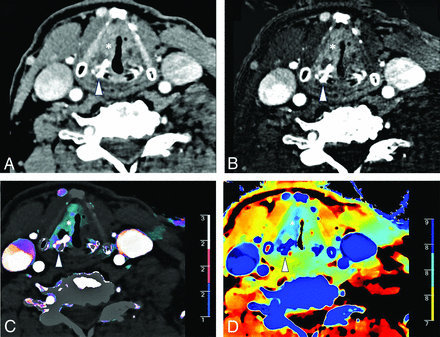

A 61-year-old man with left oral tongue squamous cell carcinoma (arrow) seen on a conventional CT image (A). Iodine density (B), color iodine density overlay (C), and Z-effective (D) images show markedly improved contrast resolution of the tumor from the surrounding normal oral tongue mucosa. The left oral tongue tumor has an iodine density = 2 mg/mL and a Z-effective value = 8.33. Normative oral tongue mucosa values from the healthy control cohort are iodine density = 0.92 mg/mL and Z-effective value = 7.67.

A 70-year-old man with left vocal cord squamous cell carcinoma (asterisk) and asymmetric sclerosis of the right arytenoid cartilage (arrowhead) seen on a conventional CT image (A). Iodine density (B), color iodine density overlay (C), and Z-effective (D) images reveal right paraglottic fat involvement with increased iodine density. The patient was upstaged from T2 to T3.